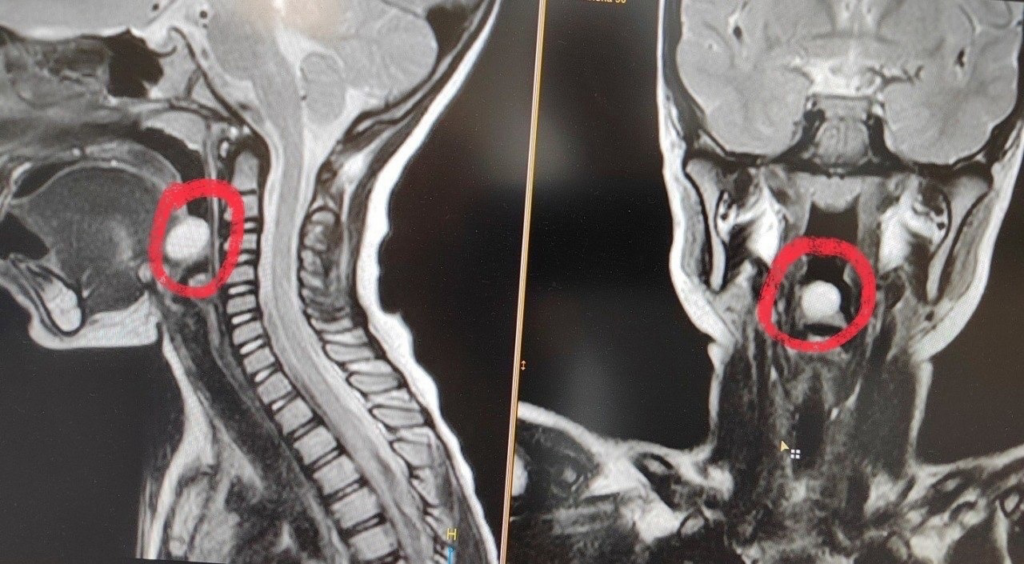

В начале года в оториноларингологическое отделение Воронежской областной детской клинической больницы №1 (ВОДКБ №1) поступила 5-летняя девочка с жалобами на затруднение при глотании. При профилактическом осмотре ЛОР-врач заподозрил новообразование надгортанника и направил в дневной стационар онкогематологии ВОДКБ №1. Там врачи провели ребенку эндоскопическое обследование и МРТ с контрастированием, что позволило определить диагноз: киста надгортанника. Медики приняли решение об эндоскопическом удалении новообразования.

Отметим, что киста надгортанника часто выявляется случайно. При увеличении размеров этого доброкачественного новообразования у пациента возникают ощущение инородного тела в горле и дискомфорт при глотании.

Врачи отметили, что киста надгортанника является достаточно редкой патологией в детской оториноларингологической практике. В России таких случаев описано совсем немного. А в практике ВОДКБ №1 это и вовсе единственный случай за последние 15 лет.